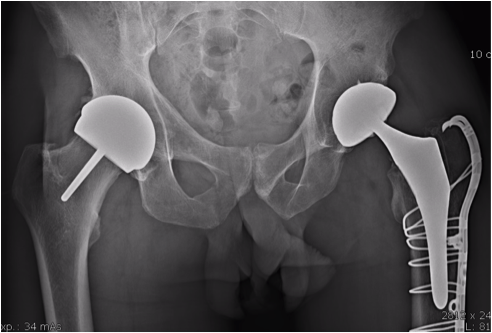

Le resurfaçage de hanche est un remplacement articulaire qui diffère d'une prothèse totale de hanche classique. Dans le resurfaçage, le col fémoral est conservé et la tête fémorale n'est pas retirée mais retaillée pour recevoir l'implant. Au niveau du bassin, la cavité acétabulaire est moins creusée que pour une prothèse conventionnelle. Cela aboutit à une économie maximale du stock osseux.

Cupule de resurfaçage de hanche

Cupule de resurfaçage

Prothèse de resurfaçage de hanche

Prothèse de resurfaçage en place